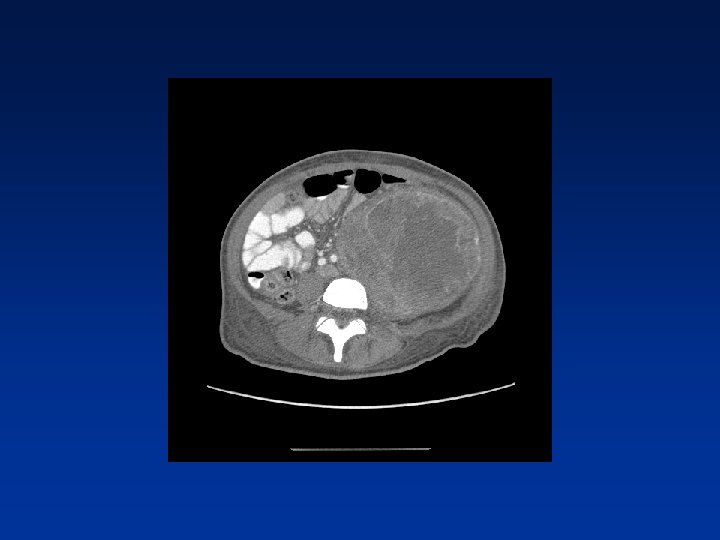

CASE